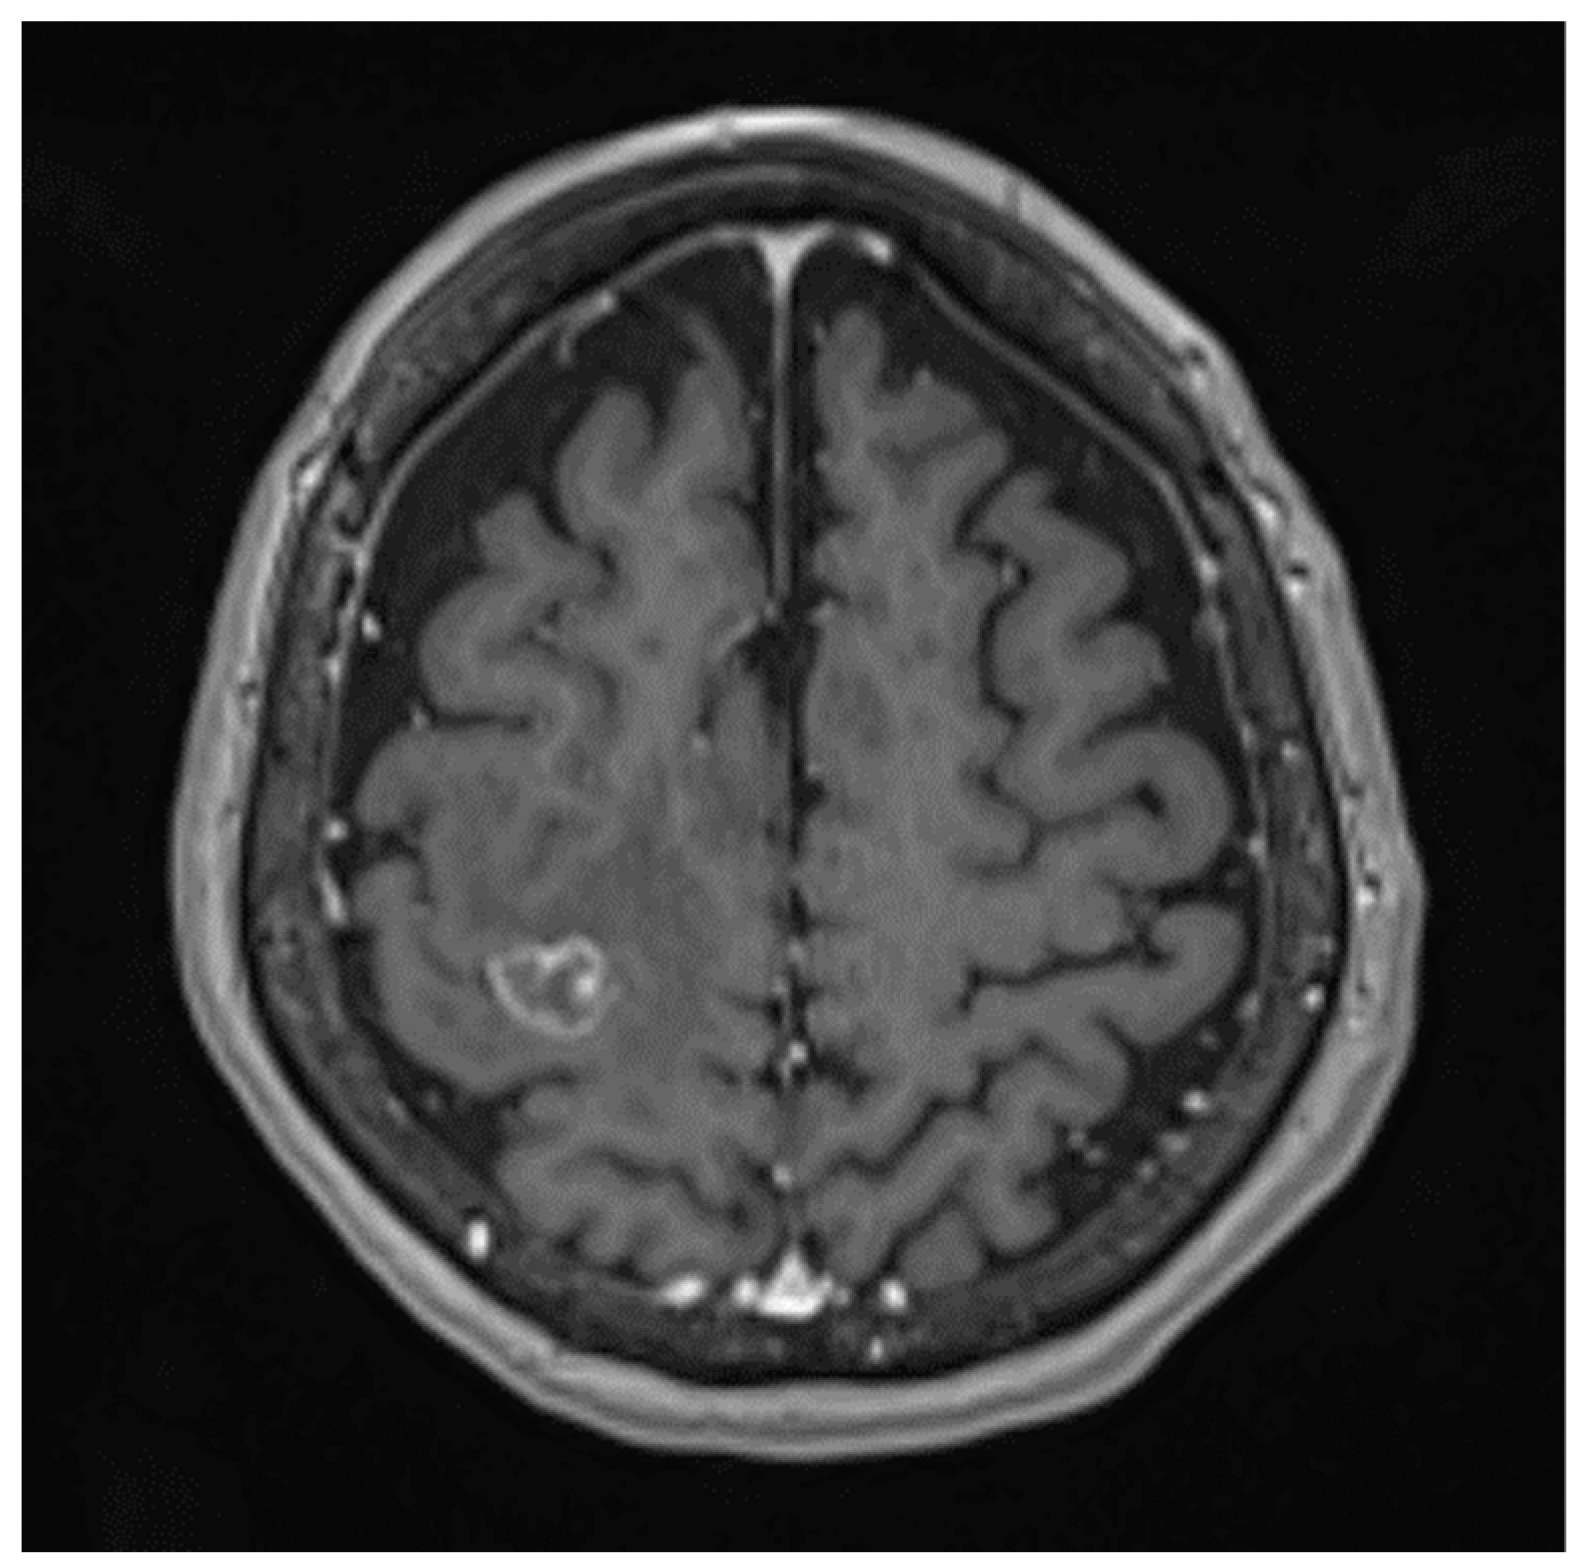

Brain metastases (BrM) occur in approximately 20~40% of cancer patients during the course of disease [1,2,3]. The median survival is approximately 3–6 months following whole-brain RT (WBRT) [2,4], 11 months following stereotactic radiosurgery (SRS) and 2 months with supportive care only [5]. Common symptoms of BrM include headache, nausea, seizure and neurocognitive impairments, which have a major negative impact on patients’ quality of life (QoL) [6]. The treatment for patients with BrM remains an integral balance between life expectancy and patients’ QoL. Figure 1 displays a solitary BrM on MRI.

Figure 1. Solitary BrM on T1-weighted MRI with gadolinium.